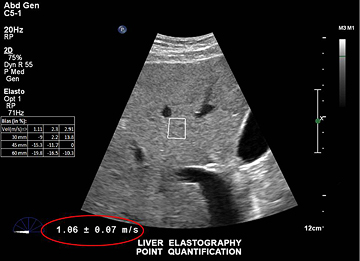

ElastPQ is an easy-to-use method of obtaining tissue stiffness values of the liver on a predefined ROI. Using real-time imaging as a guide, the ROI is placed over the area of interest and tissue stiffness data such as AVG, MEAN, and IQR are obtained and displayed in seconds. Multiple samples can be recorded and liver tissue report generated from the results.

Philips elastography generates shear waves inside the liver by using acoustic force from a focused ultrasound beam. The system monitors shear wave propagation and measures its velocity, then displays it in a format that is easy to interpret.